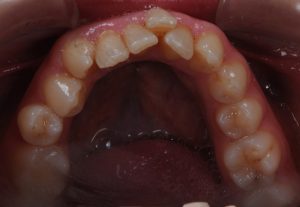

Maloclusión

Se caracteriza por una alineación incorrecta de los dientes, donde los dientes superiores e inferiores están en una relación normal, pero hay una falta de espacio que provoca que los dientes se solapen o estén apiñados.

Este problema puede generar dificultad para mantener una correcta higiene dental y afectar la estética de la sonrisa